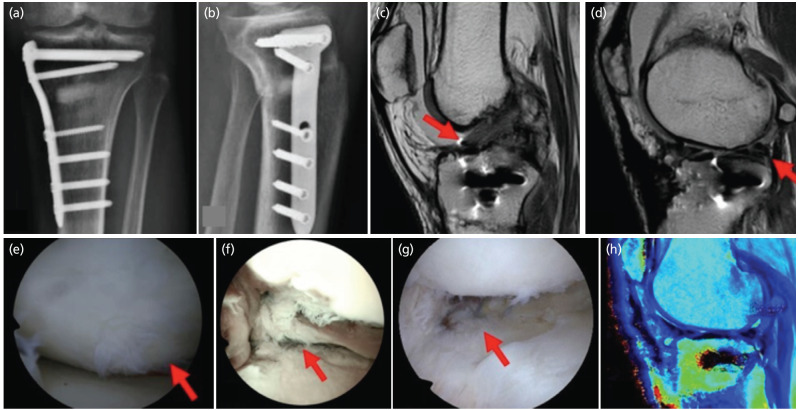

不同的手术技术用于保护膝关节软骨退化;然而,结合这些技术可能具有挑战性。本病例描述了一名35岁男性,双膝内翻错位并伴有左膝疼痛,诊断为股骨外侧4级软骨病变,复杂外侧半月板病变,内侧半月板径向撕裂。患者采用胫骨近端三维模型行外翻胫骨截骨术、外侧骨软骨异体移植和外侧半月板异体移植。术后17个月,他经历了扭转创伤,导致移植的半月板后根撕裂和前交叉韧带损伤。随后的手术探查显示了软骨保护改变的证据,包括同种异体股骨骨软骨移植愈合和移植半月板的生物力学整合,如半月板外侧根撕裂发展所示。本病例强调了结合这些外科手术实现移植半月板生物力学整合的潜力,有助于累积软骨保护作用。

Different surgical techniques are used to preserve knee articular cartilage deterioration; however, combining these techniques can be challenging. This case study describes a 35-year-old man with bilateral genu varum malalignment and left knee pain, diagnosed with a grade IV chondral lesion in the lateral femur, a complex lateral meniscus lesion, and a radial tear in the medial meniscus. The patient underwent a valgus-producing tibial osteotomy, lateral osteochondral allograft transplantation, and lateral meniscal allograft transplantation using a 3D model of the proximal tibia. Seventeen months post-operatively, he experienced torsional trauma, leading to a tear of the transplanted meniscus posterior root and an anterior cruciate ligament injury. Subsequent surgical exploration revealed evidence of chondroprotective changes, including femoral osteochondral allograft healing and biomechanical integration of the transplanted meniscus, as indicated by the lateral meniscus root tear development. This case highlights the potential of combining these surgical procedures to achieve biomechanical integration of the transplanted meniscus, contributing to cumulative chondroprotective effects.